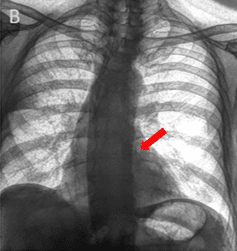

Clinical studies have evaluated the ability of spectral chest radiography to visualize coronary artery calcium.

Clinical evaluations comparing spectral radiography images with traditional X-ray have suggested:

- Opportunistic visualization of CAC and valve/vascular calcium with up to a 61.8% increase in sensitivity compared to standard X-ray, and an AUC of 91% relative to low dose CT¹⁰

- Higher sensitivity and reader agreement for detecting coronary artery calcification¹¹, ¹².

- Dual-energy chest X-ray showed improved performance over standard X-ray, with results approaching those of non-gated CT for detecting coronary calcification¹¹, ¹²

Coronary artery calcium becomes visible in the SpectralDR bone image and is confirmed on CT.